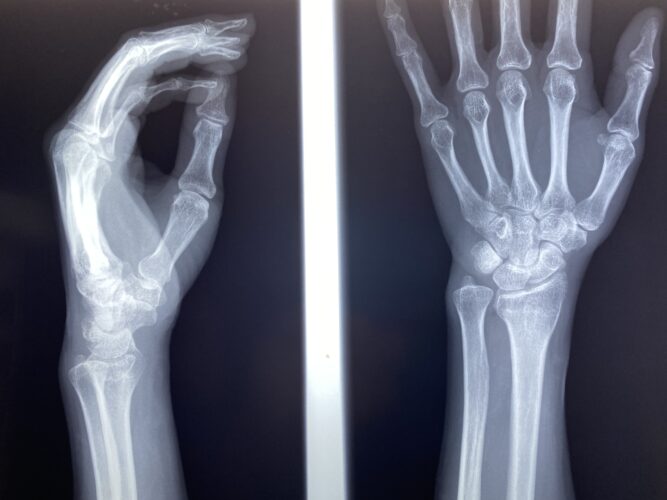

骨折・脱臼

【橈骨遠位端骨折】コーレス骨折の治療とリハビリ|手術以外の選択肢と後遺症…

保存療法を選択した場合の上腕骨顆上骨折(伸展型)の特徴や注意点について

■骨折や脱臼などの怪我の患者様の施術を数多く経験しております。

骨折・脱臼に関する研修会の役員をしています。同じ役員の先生方と講師のもと、同業の先生達に向けて骨折・脱臼の治し方の実技指導をしております。